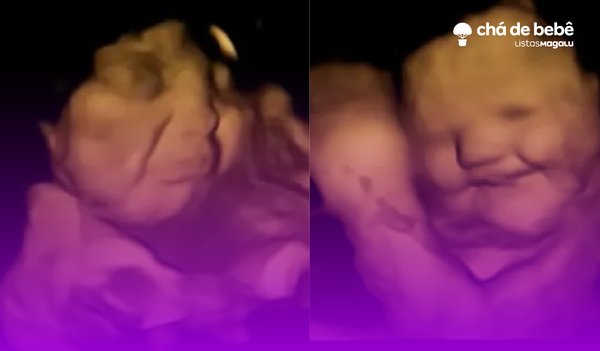

De acordo com o estudo, os fetos, a partir de 25 semanas de gestação, começam a desenvolver reações faciais ao serem expostos a diferentes sabores. Essas expressões podem incluir contrações nos músculos faciais e mudanças no semblante do bebê, algo que pode ser observado por meio de imagens de ultrassom 4D.

É fascinante pensar que, mesmo no útero, os bebês já estão começando a expressar suas reações ao ambiente e, mais especificamente, ao que está sendo ingerido pela mãe.